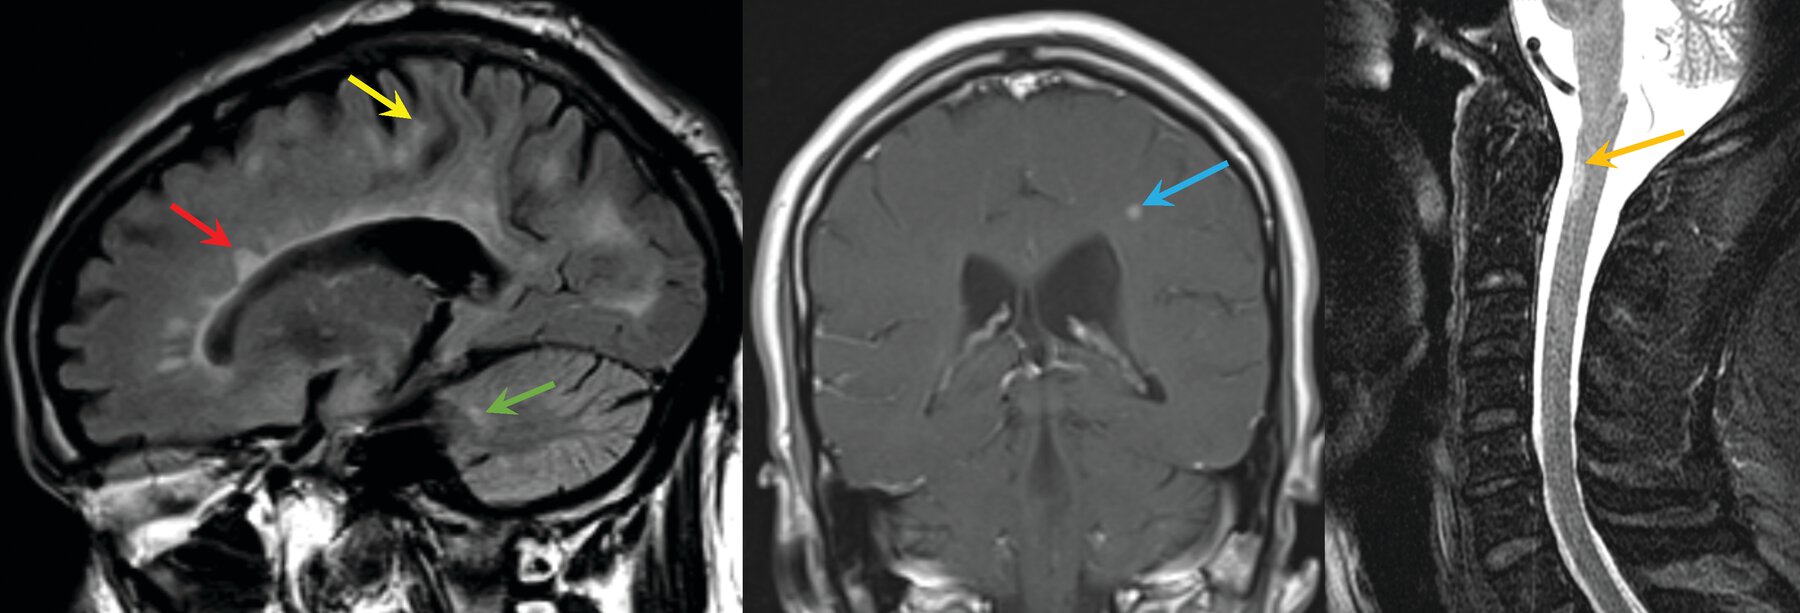

Diagnose the condition. What is the criteria to diagnose?

• The McDonald criteria for diagnosing multiple sclerosis require symptoms of central nervous system demyelination separated in space and time from a series of clinical relapses or progression, signs on physical examination, distribution of lesions on MRI, and (if necessary) the presence of CSF-unique oligoclonal bands.

• Proper application of diagnostic criteria can prevent unnecessary neurologic testing, referrals, and misdiagnoses in patients suspected of having multiple sclerosis.